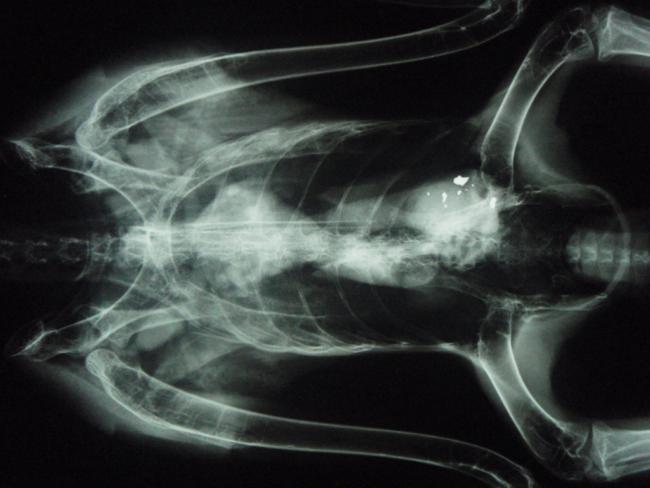

Many species of wildlife are exposed to lead in the environment, sometimes with devastating consequences. Some impacts are highly visible and well-documented, but many lesser-known species may be heavily impacted by lead poisoning too. Active surveillance is used to minimize the harms of lead poisoning, particularly in children. We aim to develop a system of active surveillance for lead poisoning in wildlife based on wildlife rehabilitation patients and hunter-harvested waterfowl.